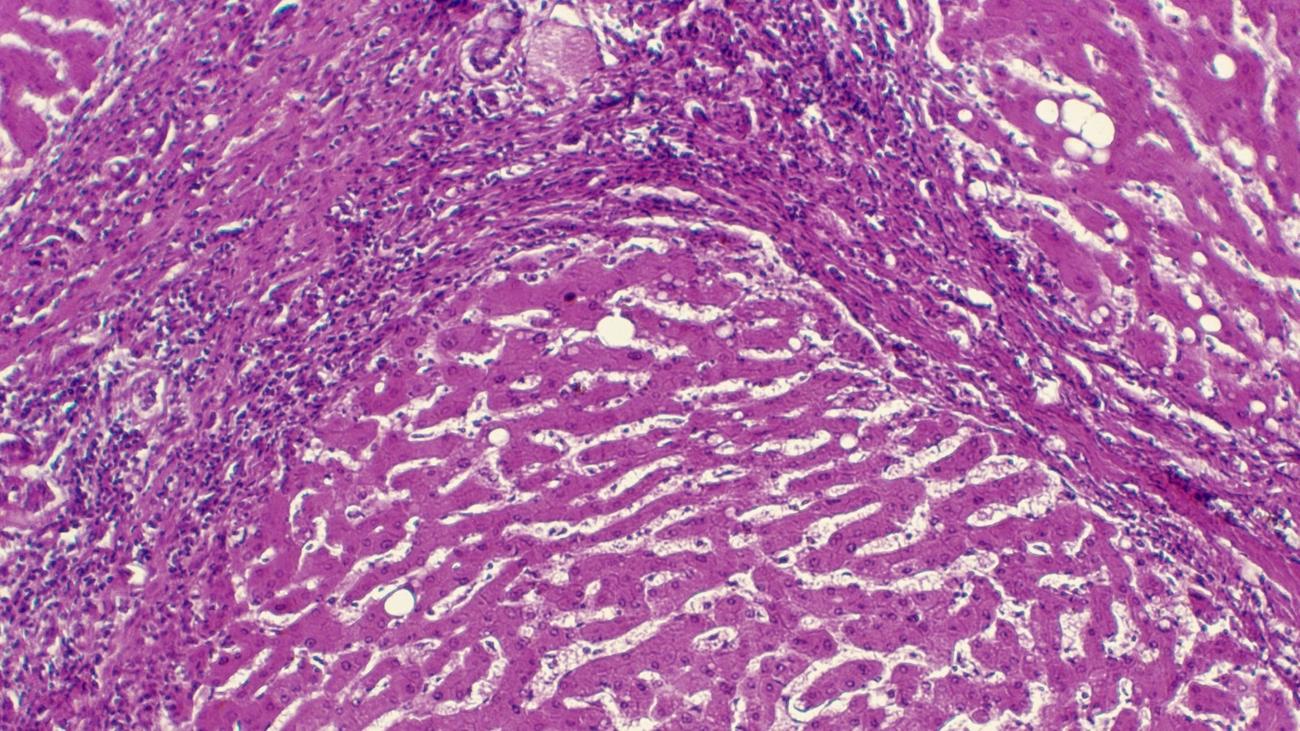

Η ασθένεια προκαλείται συνήθως από χρόνια υπερβολικής κατανάλωσης αλκοόλ, αν και μερικές φορές μπορεί να εμφανιστεί μετά από μια σύντομη περίοδο βαριάς χρήσης αλκοόλ. Συχνά δεν υπάρχουν συμπτώματα μέχρι αργά στη νόσο, όταν μπορεί να εμφανιστεί αδυναμία, σύγχυση και ίκτερος.